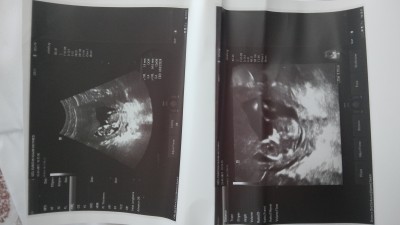

Cinsiyet 15+5 nee

Cinsiyetine bakar mısınız

Gebelik haftası

15 cinsiyet tahmin edebilen

Kiz gibi canim bacak arasi duz duruyot

Erkeğe benzetti doktorum sağlıkla gelsin inşallah rabbim kimsenin kucağını boş bırakmasın